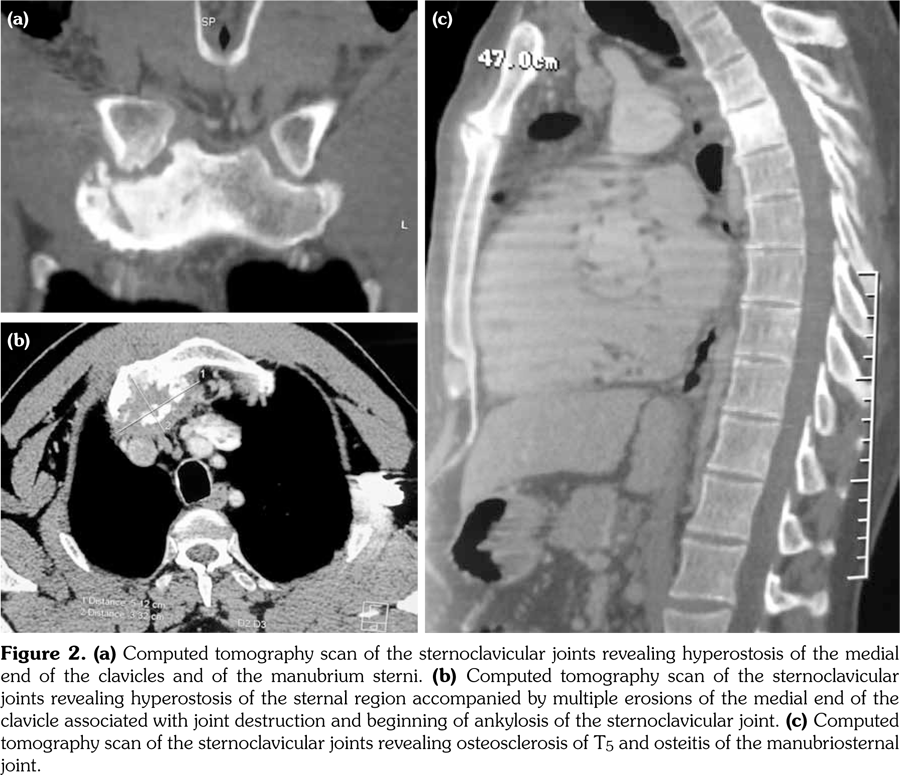

Laboratory examination revealed a slightly elevated C-reactive protein level (16 mg/L) and erythrocyte sedimentation rate (40 mm). Serum levels of calcium, albumin and phosphorus were within the normal range. Blood cell counts, liver tests, and renal function were unremarkable. Blood cultures, urinanalysis, tumor markers, and serodiagnosis for brucella were negative. Tuberculosis skin test was negative. Spine magnetic resonance imaging showed low T1, high T2 signal and contrast enhancement in the T4/T5 and L3 vertebral body and in the T4/T5 disk (Figure 1). Sacroiliac joints were normal. Computed tomography-guided biopsy of the T4/T5 disc demonstrated nonspecific inflammation and culture of this specimen was negative. Computed tomography scan of the sternoclavicular joints revealed hyperostosis and erosions involving the sternum as well as medial end of clavicle (Figure 2). Clavicular biopsy showed irregular sclerotic trabeculae. Human leukocyte antigen B27 typing was positive.